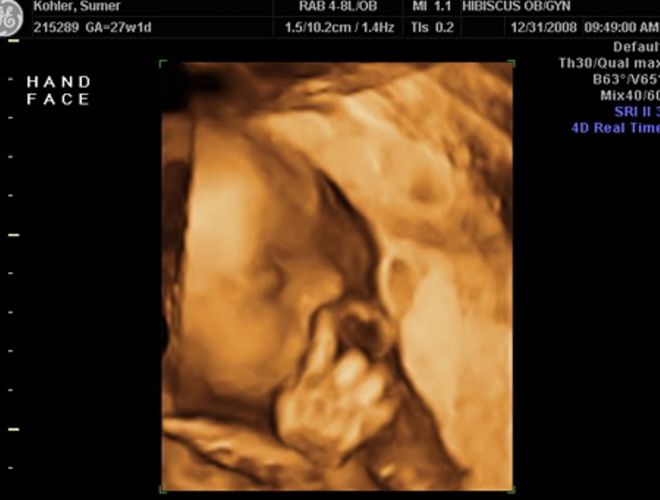

Կարծես թե այս փոքրիկն ինչ-որ բա՞ն է փորձում ասել։